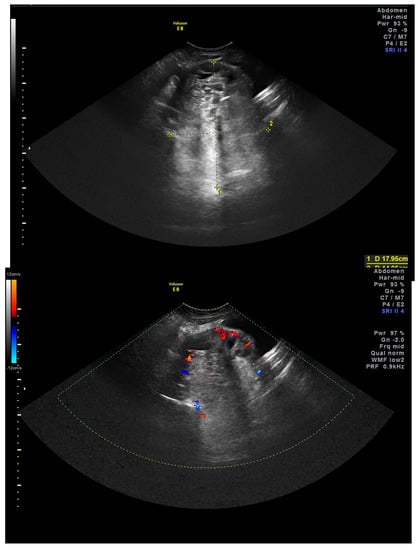

2. Case Presentation